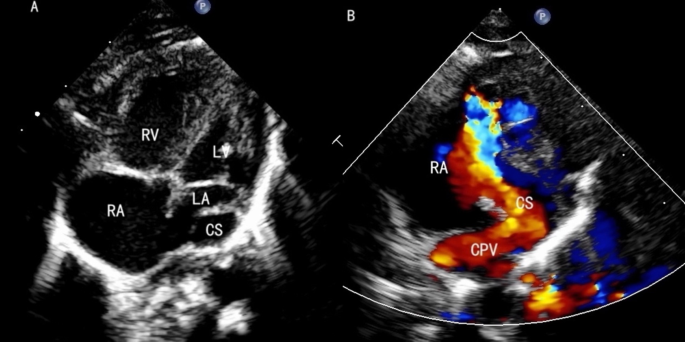

All 48 cases underwent echocardiographic examination to evaluate the pulmonary venous drainage pathways, the presence of obstruction, associated malformations, and cardiac function. Among the 15 supracardiac types, nine cases drained into the innominate vein and six into the superior vena cava (SVC) (Fig. 1). There were 13 single vertical vein and 2 cases of double vertical veins. In the 20 cardiac cases, 17 CPVs drained into the RA via the coronary sinus (CS) (Fig. 2), two CPV drained directly into the RA, and one had four pulmonary veins draining separately into the RA. Among the 10 infracardiac cases, eight cases had CPVs that drained into the portal vein via a vertical vein, one drained into the hepatic vein, and one drained into the inferior vena cava via ductus venous (Fig. 3). In the three cases mixed-type cases, all of them combines both supracardiac and cardiac types (Fig. 4).

The echocardiography of cardiac TAPVC. (A) The CS is dilated behind the small LA. (B) The CPV drains into the CS.